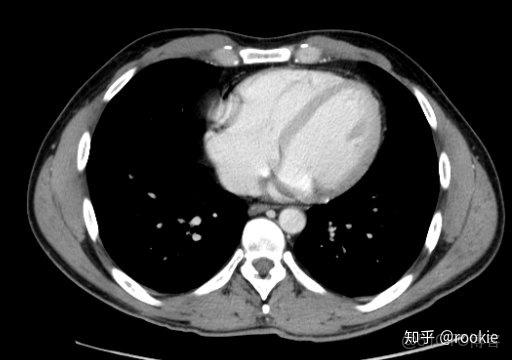

縱隔窗口窗口設置: (W:500,L:50)優點: 這些設置在本質上與軟組織設置或腹部設置相似,並進行了微調,以儘可能清晰地顯示出縱隔病理。

CLAHE算法增強局部對比度的X光圖像增強效果對比_#python 計算對比度_13

縱隔窗與腹部或軟組織窗相似,但稍作調整以顯示縱隔結構。